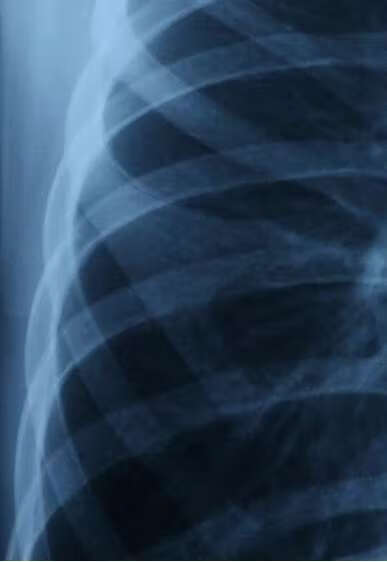

(1)X线:对于肋骨即有分叉的患儿通常拍胸部X线片即可显示畸形肋骨(如图1),表现为肋骨与肋软骨交界处硬肋的增宽或分叉。对于软骨分叉的患儿,由于软骨组织的特性,通常X线不能很好显示。